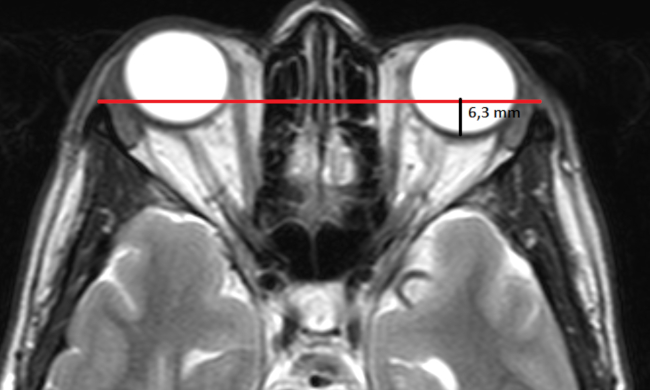

Proptosis

La proptosis es el desplazamiento o protrusión anterior del globo ocular. El término exoftalmos es empleado como sinónimo de proptosis, aunque suele relacionarse con las oftalmopatías endócrinas.27

La propotsis puede cuantificarse empleando cortes axiales de TC o RM, donde se aprecie al globo ocular en sus diámetros máximos (incluso en forma prenatal).27,28,29,30

Para ello, se traza una línea recta entre los dos procesos cigomáticos (línea intercigomática). Luego se realiza otra línea (perpendicular a la intercigomática) hacia la esclera posterior: el valor promedio normal es 9,9 +/- 1,7mm (►Fig. 11).27,28,29,30

La distancia entre la línea intercigomática y el borde anterior del globo ocular debe ser menor a 21-23 mm (►Fig. 12).27,28,29,30